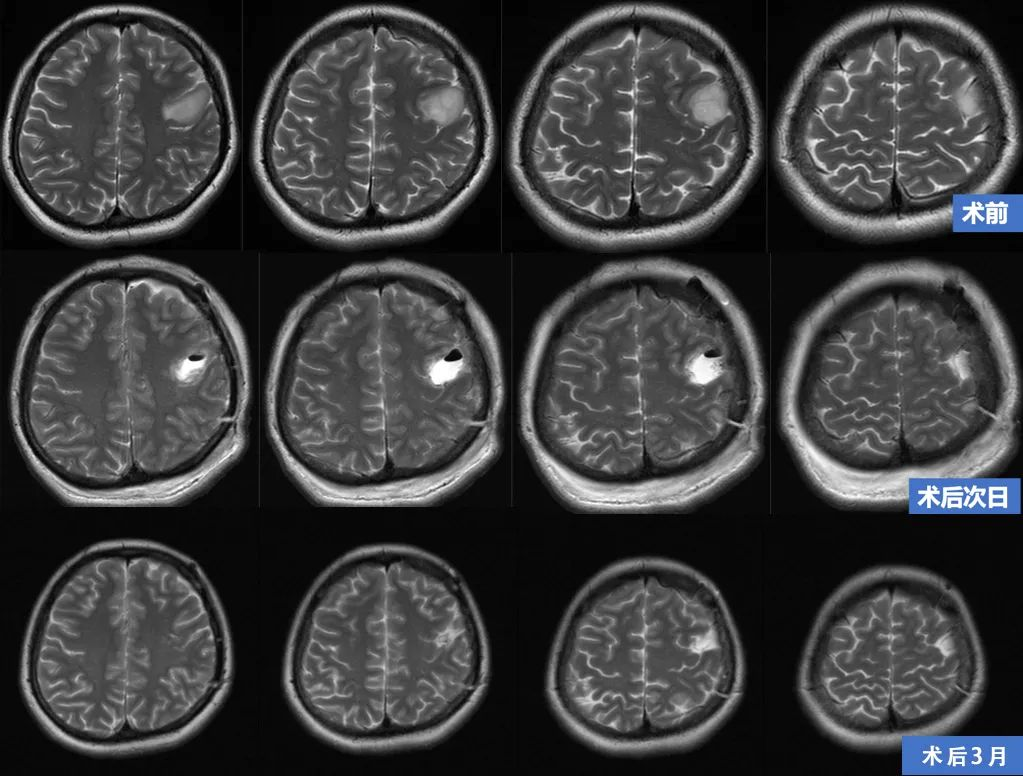

术前磁共振:

肿瘤位于左中央前回中端偏腹侧,长T1长T2,无明显强化,低灌注

• 术后当日患者出现语言减慢的症状,无明显肢体运动障碍。

• 术后4天出现右手、口角麻木的症状。

• 术后5天出现右手活动不灵活的症状。

• 术后7天麻木和肢体活动均好转痊愈,言语稍迟缓。